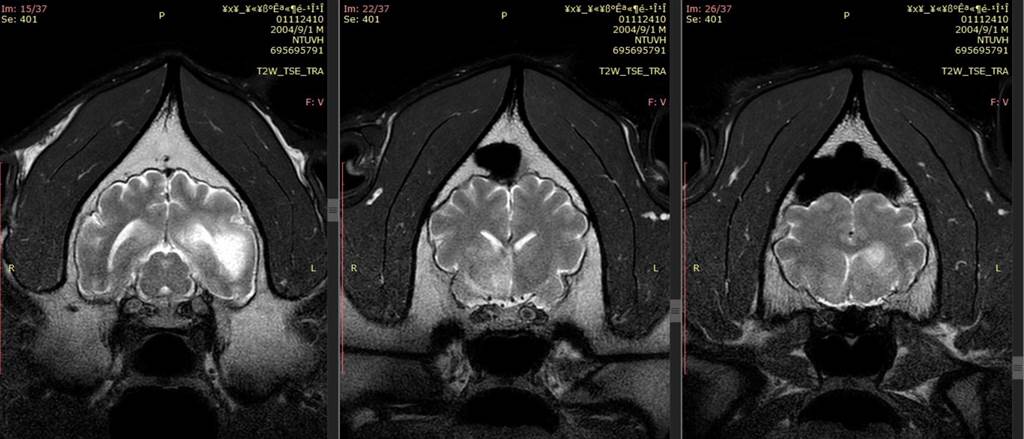

報道稱,“團團”第二次核磁共振結果已經出爐,影像顯示其腦部病變除既有的病灶外,區域明顯擴大,且出現腫塊;其病情發展快速,推測其腦部患惡性腫瘤的可能“大幅提高”。台北市動物園考慮到“團團”近期的臨牀表現與此次對麻醉反應、甦醒恢復時間延長等,決定不再對它進行麻醉或侵入性檢查,將以維護動物福利為優先,採用舒緩方式照顧。

大熊貓“團團”和“圓圓”於2008年12月赴台,其中“團團”為雄性。台北市動物園今年8月30日為它們舉辦了18歲生日慶祝活動。“團團”8月下旬發生癲癇症狀,經核磁共振檢查,發現其左右大腦半球均有局部液化病變壞死。